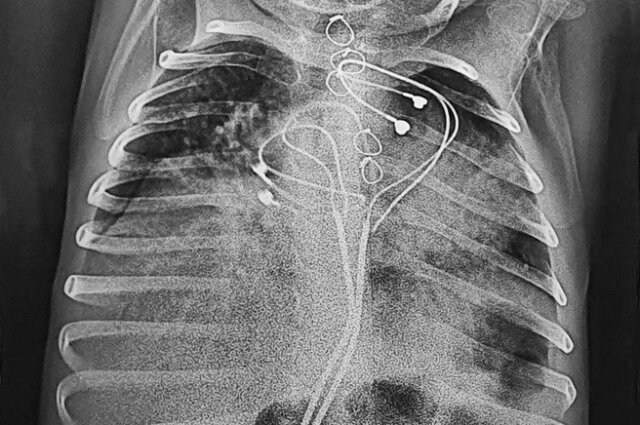

Уникальную операцию 3-летнему малышу провела объединенная бригада врачей Центра Мешалкина и Новосибирской областной больницы.

Малыш родился с редкой формой аритмии, встречающейся один раз на 25 тыс новорожденных. Для поддержания жизнеспособности на второй день после рождения ему был имплантирован кардиостимулятор.

Аппарат установили в верхней части живота, так как в грудной клетке младенцев его невозможно разместить. Спустя три года ребенок попал в одну из клиник Барнаула с высокой температурой и кишечной непроходимостью.

Обследование показало невероятное: стимулятор, проникнув сквозь мышцы, мигрировал в кишечник. При этом аппарат продолжал работать и задавать нужный ритм сердцу ребенка. Кардиостимулятор не покинул организм естественным путем благодаря проводам и электродам, которые тянулись за ним от сердца.

Фото: НМИЦ им. академика Е. Н. Мешалкина/ Пресс-служба

В ходе операции хирурги извлекли аппарат, очистили кишечник от спаек, а в грудную клетку установили новый стимулятор. Спустя 10 дней мальчика выписали из медучреждения.

В Центре Мешалкина рассказали, что подобная ситуация в практике российских врачей встречается впервые.